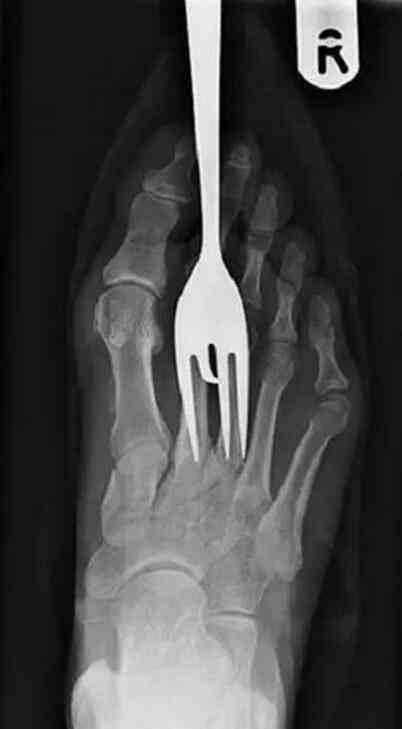

这是剔牙时候掉进去的,还有这操作